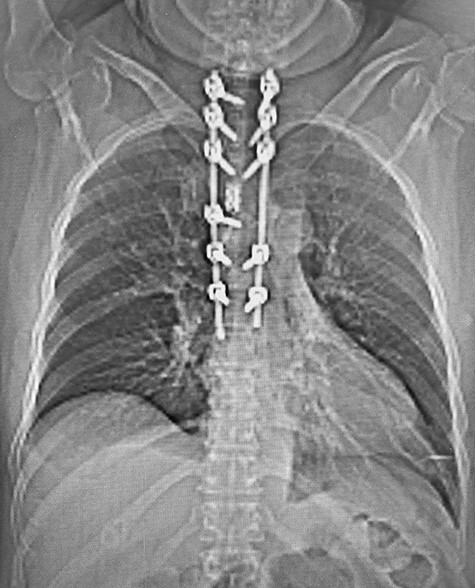

Post-operative CT with reconstructed anteroposterior view of the T1–T7 pedicle screw fixation and expandable titanium cage in situ.

Post-operative, sagittal CT images of the T1–T7 pedicle screw fixation and expandable titanium cage in situ.